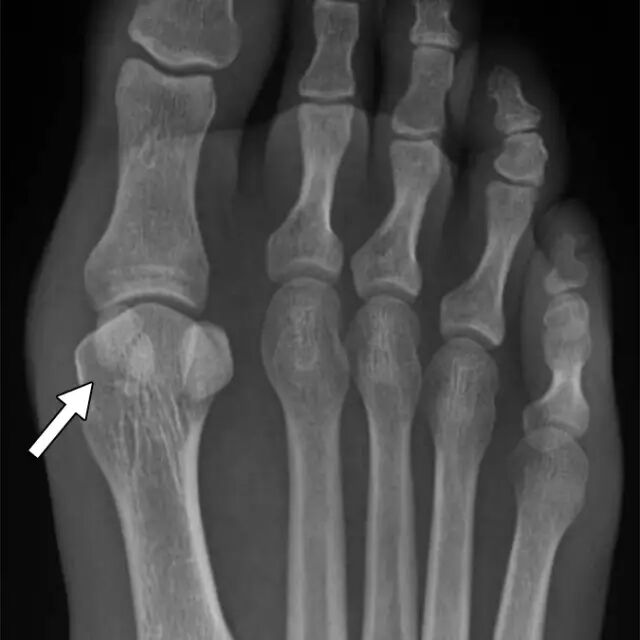

脚本身有一些最复杂的骨骼解剖,与多个奇怪形状的骨头相互重叠。一些足部骨折的微小性质和复杂的解剖结构可能导致脚的错过的骨折的增加的倾向。小骨软骨骨折的距骨穹顶或小的撕裂骨折周围的后足和中足可能很难找到[21]。后足和中足的解剖结构使其难以识别骨折,特别是距骨[22](图5),立方体(图6),楔形体[23-25],跟骨的前过程[26]和Lisfranc关节[27]。

图 6-35岁的女人,脚后疼痛。A,在X光片,包括侧位片,骨折很难看到,甚至在事后。B,在这个矢状面CT重建中观察到第四跖关节(箭头)处的立方体的关节内骨折。